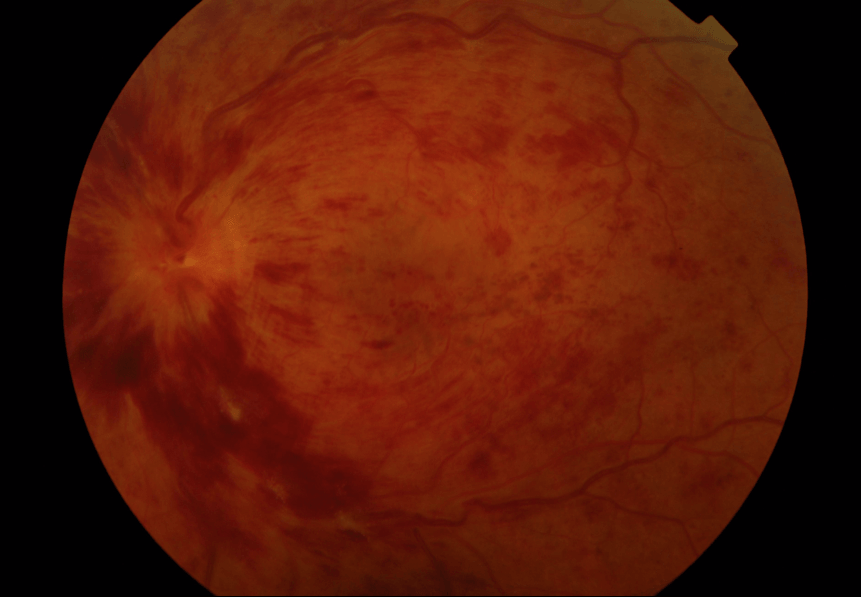

Write your caption hereButton